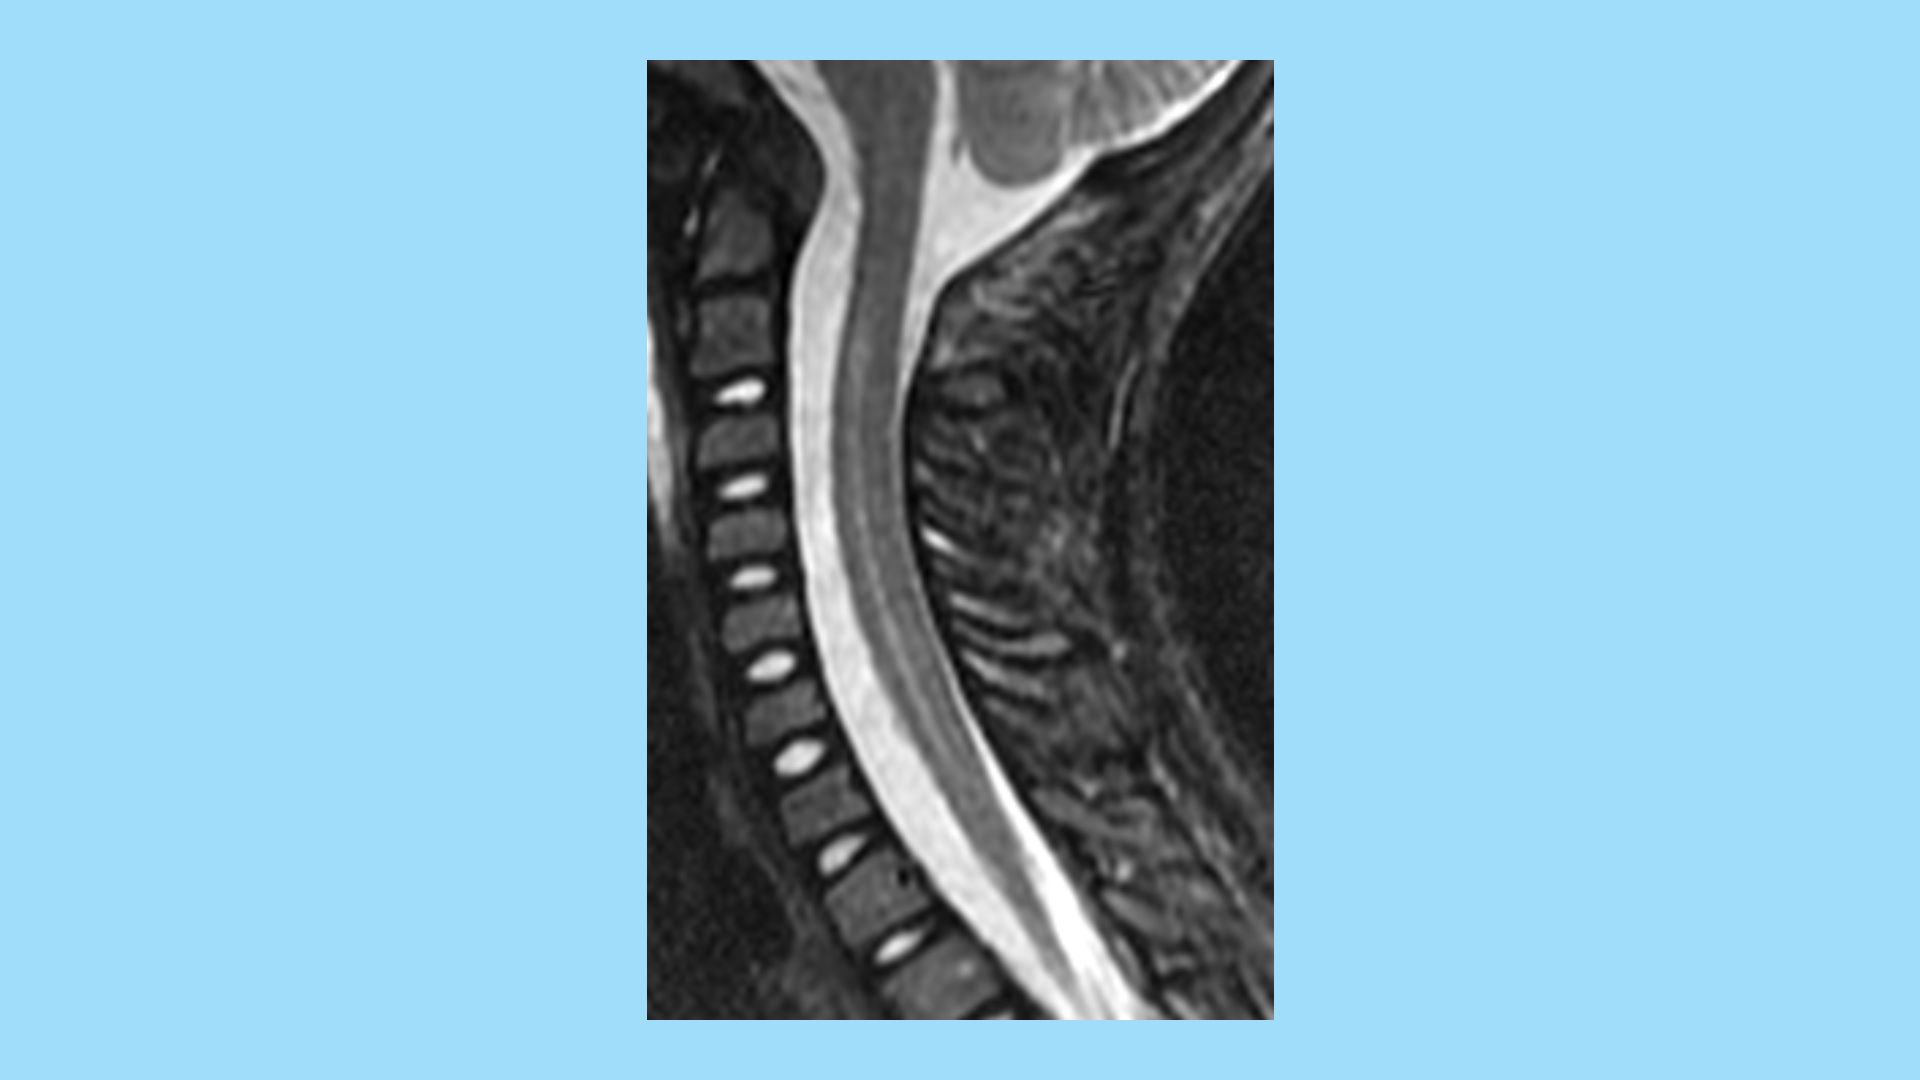

Public health officials are escalating their hunt for the cause of a mysterious ailment afflicting young children, known as acute flaccid myelitis (AFM). Cases of AFM have spiked recently, leaving some young children with partial paralysis and muscle weakness.

Why it matters: While the illness remains very rare, there are currently 127 suspected and 62 confirmed cases in 22 states, according to the Centers for Disease Control and Prevention. And — despite years of testing prior cases — the cause of the illness is "still a mystery," Anthony Fauci, director of the National Institute of Allergy and Infectious Diseases, tells Axios.